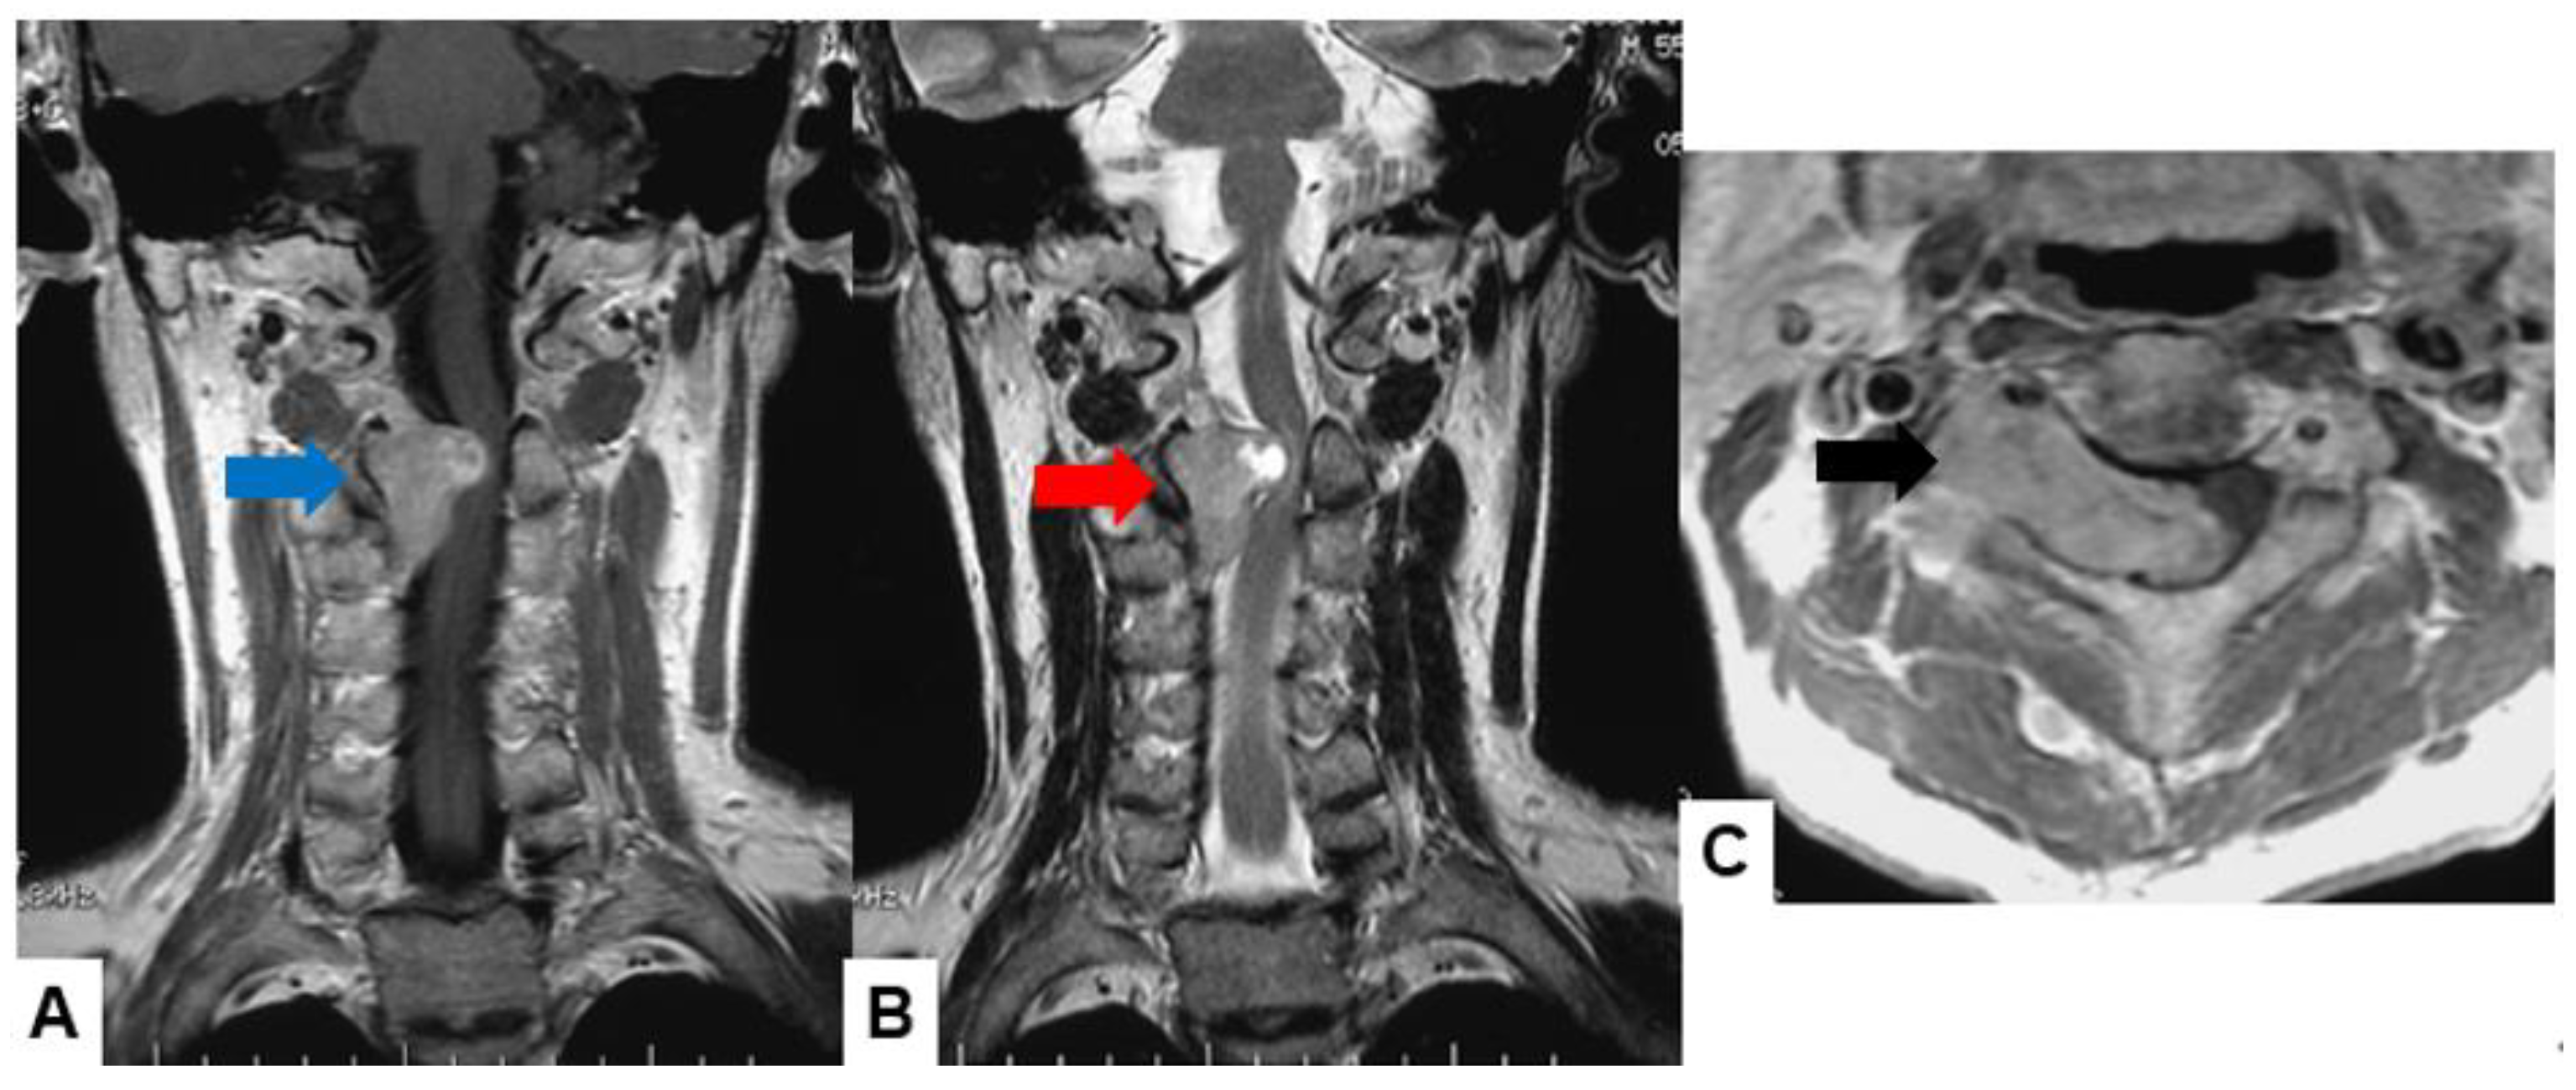

Schwannomas usually show low intensity in T1-weighted MR imaging and high intensity in T2-weighted MR imaging (Figure 1 and Figure 2). These tumors often enlarge alongside the nerve root and become a dumbbell-type [34]. The heterogenicity of a tumor indicates cystic change.

Fifty-four M, spinal schwannoma. (A) T1-weighted midsagittal image, (B) T2-weighted midsagittal image, and (C) enhanced T1-weighted midsagittal image. Red arrows indicate tumor and blue arrow shows tumor enhancement. The tumor is mixed-intensity because of tumor necrosis.

Fifty-five M, spinal schwannoma. (A) Enhanced T1-weighted midsagittal image, (B) T2-weighted midsagittal image, and (C) enhanced T1-weighted axial image at C2/3. Red arrow indicates tumor and blue arrow shows tumor enhancement. The tumor is dumbbell-shaped (black arrow).